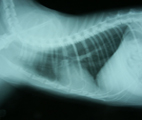

初診時胸部X線所見。心陰影拡大とスリガラス陰影あり。 第8病日さらに心陰影拡大し、心嚢液貯留が疑われた。 同日血膿様液を154ml抜去し、Pasteurella属を検出した。 退院2ヶ月後の胸部X線所見。心陰影正常で再発していない。

経過:初診時、体温:39.1℃ 心拍数:200/分 呼吸数:68/分。可視粘膜色良好。食欲元気なし。咳なし。聴診にて心音遠く感じられた。心雑音なし。肺音粗励。胸部X線にて心陰影拡大、気管分岐部挙上、肺野スリガラス陰影が認められた。動脈血ガス分析にてpH7.416, Pco2 27.3 mmHg, Po2 96.4mmHgと肺機能は保たれていた。心嚢液貯留と心機能低下による間質性肺水腫を疑い、利尿剤投与を始めた。翌日、スリガラス影は消失した。第8病日、さらに心陰影が拡大していたので、全身麻酔下、気管内挿管下にて心嚢液の試験穿刺を行った。麻酔前のCBC生化学検査ではWBC 11000/μLで左方移動認めず、ALB2.2g/dlと低下していた。伏臥位にて、透視下に22G静脈留置針を用い右第6肋間を穿刺した。計154mlの血膿様液(Ht9%, WBC>99900/μL, TP5.0g/dl)が抜去された。上清は黄色透明で比重1.033、TP5.0と滲出性、沈渣細胞診にて多数の変性好中球がみられた。培養にてPasteurella属の細菌が検出され、ABPC, AMPC, CEZ, EM, GM,AMK, MINO, OFLX, ENX, FOMに感受性を示した。由来は不明だが、化膿性心嚢液が貯留していたことが判明した。入院管理となりABPC20mg/kgとGM5mg/kgの投与を開始した。第12病日再び19mlの血膿様液を抜去したが培養にて菌は検出されなかった。それ以降心嚢液の再貯留を認めなかった。第22病日経過良好のめ退院。自宅ではバイトリル錠25mgを毎日投与してもらった。その後1ヶ月ごとに3ヶ月間継続して胸部X線心陰影を経過観察したが、再発を認めなかった。